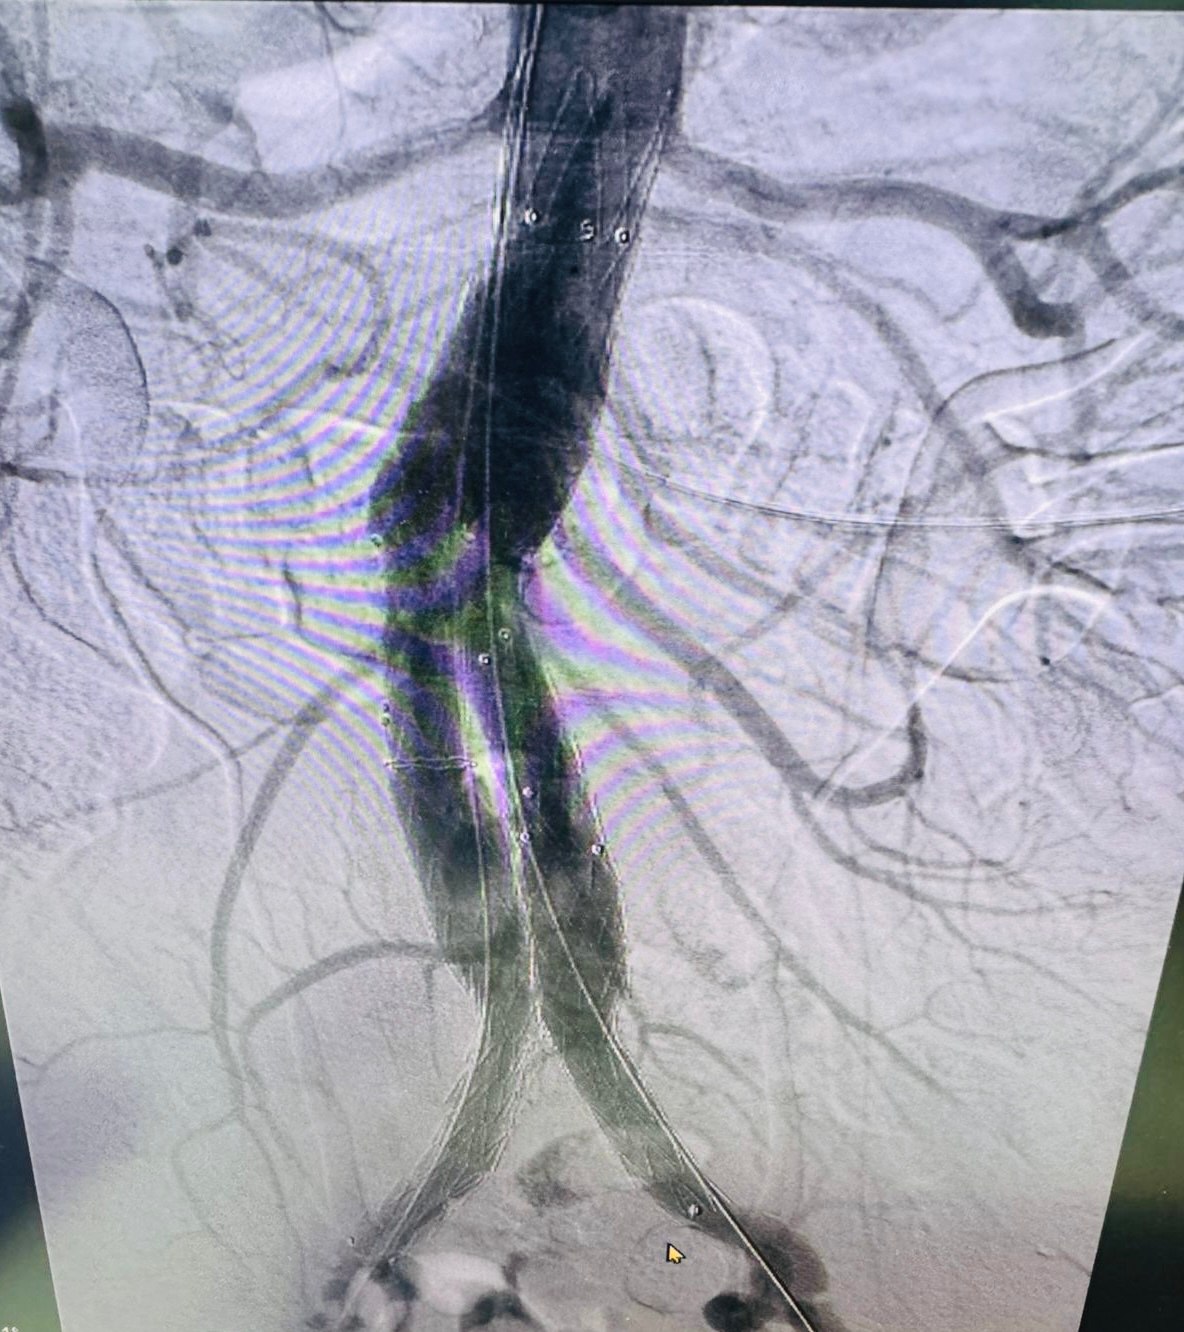

В Региональном сосудистом центре Областной больницы впервые выполнено эндопротезирование брюшной аорты.

Эндопротезирование брюшного отдела аорты — это инновационная малотравматичная методика, которая позволяет:

До недавнего времени такие вмешательства были доступны только в федеральных центрах. Теперь жители Калужской области могут получать высокотехнологичную помощь не покидая регион.

Операция выполнена руководителем центра Андреем Куликовым, заведующим отделением сосудистой хирургии Игорем Гладковым, заведующим отделением рентгенхирургических методов лечения и диагностики Андреем Колуновым и врачами отделения сосудистой хирургии.